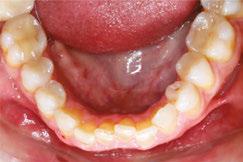

Upon closer examination, there were contributing factors that led to his discomfort. Stan had been a stomach/face sleeper for years. He also bit his nails since childhood, had a smoking habit from his youth, and he was prone to ear infections. He had moderate tongue and buccal ties, obligate mouth breathing, aggravated by a deviated septum, narrow nares, low tongue resting posture, an anterior open bite, a lower jaw that deviated upon opening, and bouts of acid reflux.

During his therapy, there was a discussion about the possible benefits he may receive from having his jaws expanded, making more room for his tongue, then to be followed by a tongue and buccal frenums release. His intermolar width is 34 mm, and his intercanine width is 25 mm. I feel any expansion has a potential benefit.

Figure 6: No room for his tongue

Figure 4: 7 years later on April 10, 2024. Anterior open bite closed a bit

Figure 2: Initial assessment on December 15, 2016 (top left). Later September 20, 2017, his anterior openbite widened (top right)